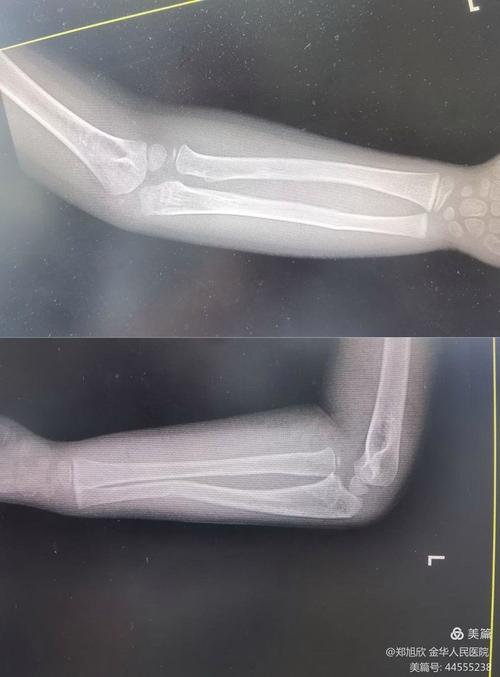

一次儿童四肢骨折X光检查的辐射剂量大约是多少?

(图片来源网络,侵删)- 一个手臂或腿部的X光检查,辐射剂量大约在 001 - 0.01 mSv 之间。

(图片来源网络,侵删)- 明确诊断: X光片是诊断骨折最直接、最准确的方法,它能清晰地显示骨折的部位、类型、移位情况,是医生制定治疗方案(是打石膏还是需要手术)的唯一依据。